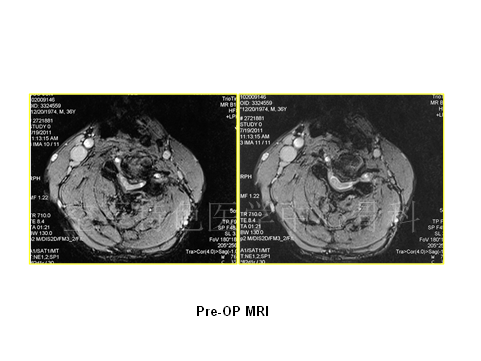

患者男性,37岁,主诉:头颈部不停抽动11年,四肢麻木无力,行走不稳 1月余。既往曾以“共济失调”入住神经内科。查体:颈3平面以下痛觉减退,双肘关节以下痛觉减退明显,胸4平面以下感觉减退。四肢肌力Ⅳ级,四肢腱反射活跃,肌张力高。双侧Hoffman’s征+,Babinski’s征+。JOA评分:9分。患者入院时头颈部不自主的扭动,行走不稳,易摔跤。

患者影像学资料如下: